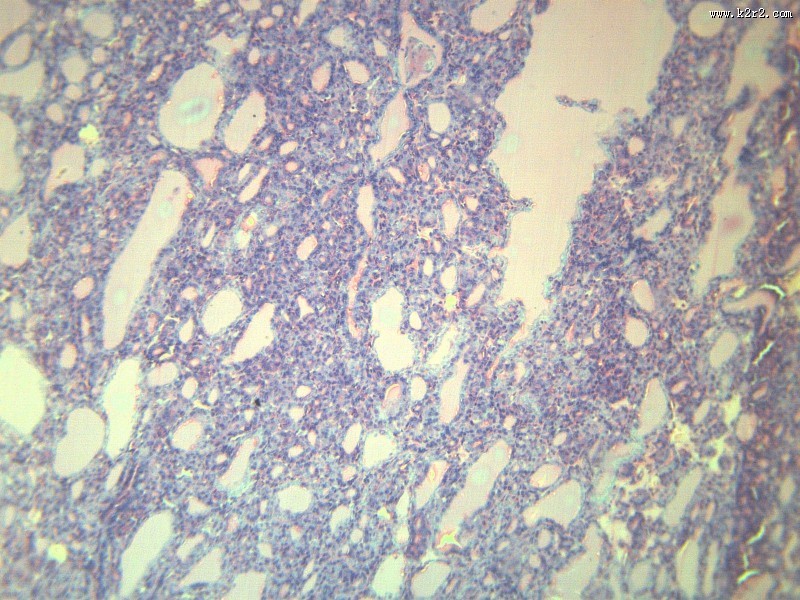

甲状腺瘤 - 第6张 共有

显微切片

肿瘤

thyroidadenoma

甲状腺瘤

腺瘤